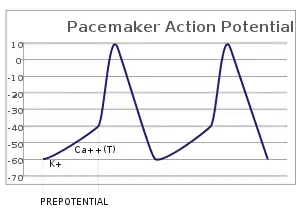

In the pacemaking cells of the heart (e.g., the sinoatrial node), the pacemaker potential (also called the pacemaker current) is the slow, positive increase in voltage across the cell's membrane (the membrane potential) that occurs between the end of one action potential and the beginning of the next action potential. This increase in membrane potential is what causes the cell membrane, which typically maintains a resting membrane potential around -65 mV,[1] to reach the threshold potential and consequently fire the next action potential; thus, the pacemaker potential is what drives the self-generated rhythmic firing (automaticity) of pacemaker cells, and the rate of change (i.e., the slope) of the pacemaker potential is what determines the timing of the next action potential and thus the intrinsic firing rate of the cell. In a healthy sinoatrial node (SAN, a complex tissue within the right atrium containing pacemaker cells that normally determine the intrinsic firing rate for the entire heart[2][3]), the pacemaker potential is the main determinant of the heart rate. Because the pacemaker potential represents the non-contracting time between heart beats (diastole), it is also called the diastolic depolarization. The amount of net inward current required to move the cell membrane potential during the pacemaker phase is extremely small, in the order of few pAs, but this net flux arises from time to time changing contribution of several currents that flow with different voltage and time dependence. Evidence in support of the active presence of K+, Ca2+, Na+ channels and Na+/K+ exchanger during the pacemaker phase have been variously reported in the literature, but several indications point to the “funny”(If) current as one of the most important.[4](see funny current). There is now substantial evidence that also sarcoplasmic reticulum (SR) Ca2+-transients participate to the generation of the diastolic depolarization via a process involving the Na–Ca exchanger.

The firing of the pacemaker cells is induced electrically by reaching the threshold potential of the cell membrane. The threshold potential is the potential an excitable cell membrane, such as a myocyte, must reach in order to induce an action potential.[6] This depolarization is caused by very small net inward currents of calcium ions across the cell membrane, which gives rise to the action potential.[7][8]